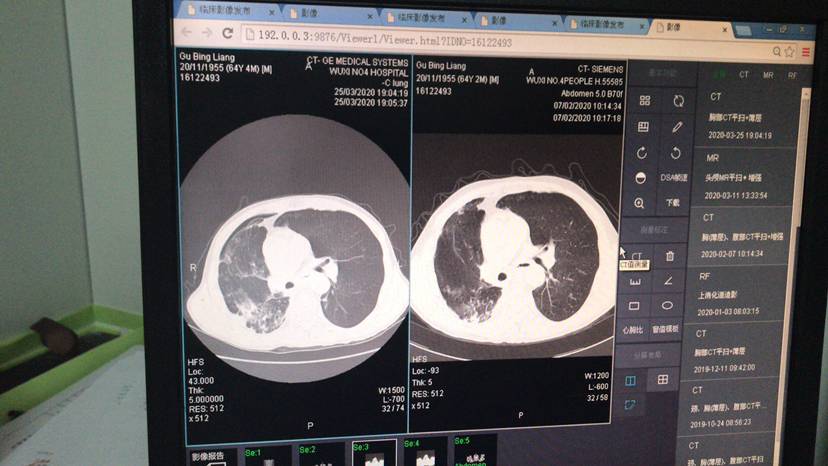

这是第四图,大家看下

白细胞数量不是很高,医生可能看到中性粒细胞比例升高,怀疑是细菌感染的肺炎。影像学肺窗显示肿瘤对比可能是免疫造成的“假性进展”。可以先继续消炎试试,消炎的话会影响免疫药效果,免疫药要暂时先停掉。建议去咨询一下呼吸科或者肿瘤科